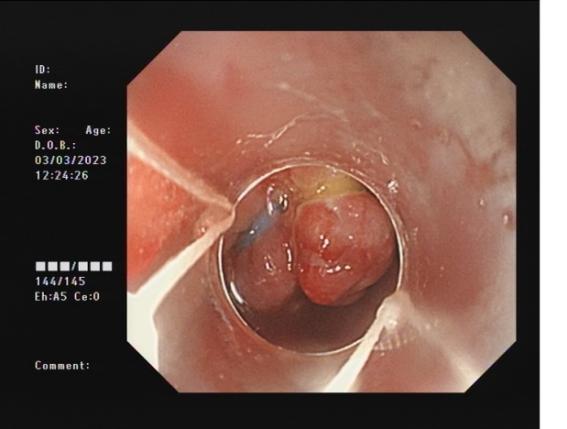

胃底間質瘤 內鏡下全層切除術后創面 切除后標本

內鏡下全層切除術(EFTR):治療消化道黏膜下腫瘤(最主要):起源于固有肌層深層、部分腔外生長、與漿膜層密不可分;少部分抬舉征陰性消化道癌前病變和早期癌;少部分困難解剖部位結腸病變(如結腸憩室內腺瘤)等。